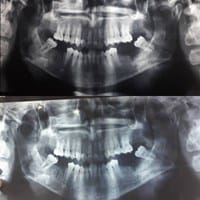

Dolor y latidos en la mandibula izquierda, puede ser atm?